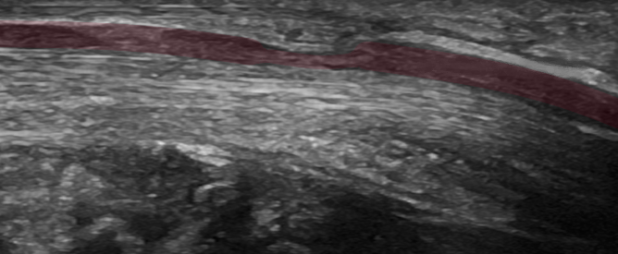

Empfohlen wird die Darstellung des Nervus medianus von der Mitte des Vorderarmes bis zum Ausgang des Karpalkanals.

Der chronische Druck auf den N. medianus im Karpalkanal bedingt eine segmentale Nervenschwellung. Die maximale Nervenquerschnittsfläche oder Cross Sectional Area (CSA) im Bereich der Karpalkanals wird gemessen. Häufig liegt diese vor Eintritt in den Karpalkanal. Neben der Nervenschwellung ist im Bereich der Druckschädigung auch die Nervenstruktur gestört. Die normale faszikuläre Struktur des Nervs, die sich sonografisch wie eine Honigwabe darstellt, ist im Falle einer Nervenkompression meist aufgehoben und der Nerv stellt sich als homogen hypoechogen dar. Ein weiterer hilfreicher nervensonografischer Parameter beim Karpaltunnelsyndrom ist die Verhältnismessung der Nervenquerschnittsfläche am Handgelenk und in der Mitte des Vorderarmes. Neben den Nervenquerschnittsflächenmessungen wird der N. medianus im Karpalkanal im Längsschnitt dargestellt mit der Frage nach einer segmentalen (sanduhrförmigen) Kompression des Nervs. Diese Darstellung ist vor allem bei anhaltenden Symptomen trotz einer bereits erfolgten Operation des Karpaltunnelsyndroms sehr hilfreich.